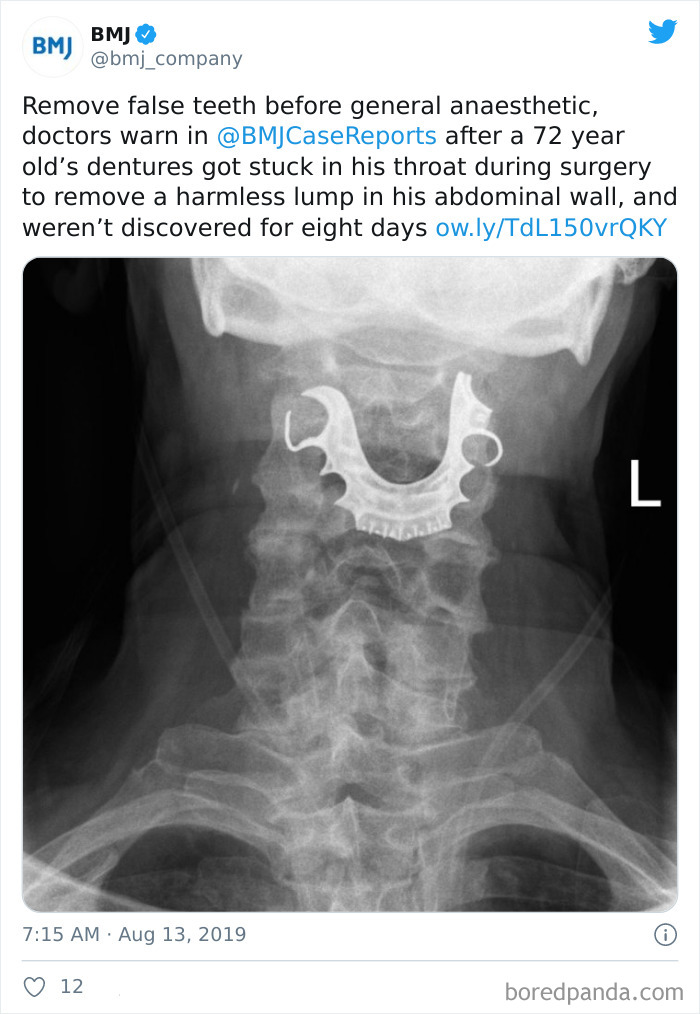

Missing Dentures Found In Man's Throat 8 Days After Surgery